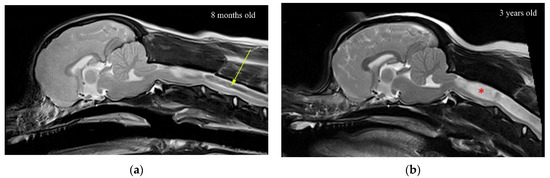

- Cirovic, S.; Lloyd, R.; Jovanovik, J.; Volk, H.A.; Rusbridge, C. Computer simulation of syringomyelia in dogs. BMC Vet. Res. 2018, 14, 82. [Google Scholar] [CrossRef] [PubMed] [Green Version]

- Rusbridge, C.; Stringer, F.; Knowler, S.P. Clinical application of diagnostic imaging of Chiari-like malformation and syringomyelia. Front. Vet. Sci. 2018, 5, 280. [Google Scholar] [CrossRef] [PubMed]